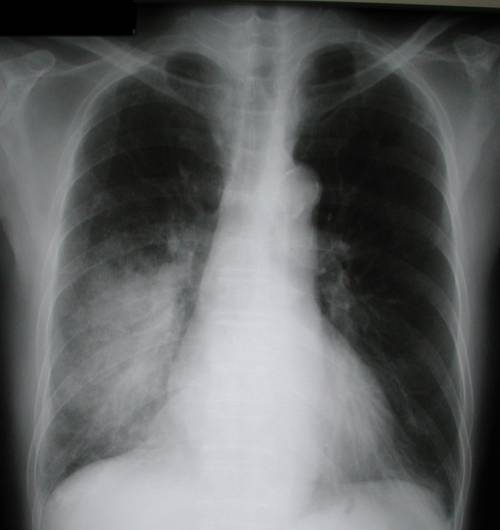

На фото рентгеновских снимок, на котором легкие с воспалением.

При повышении давления в малом круге кровообращения рентгенологически будет отмечаться расширение размеров сердца, особенно. Также на рентгенограмме можно обнаружить участки затемнения, соответствующие очагу инфекции.